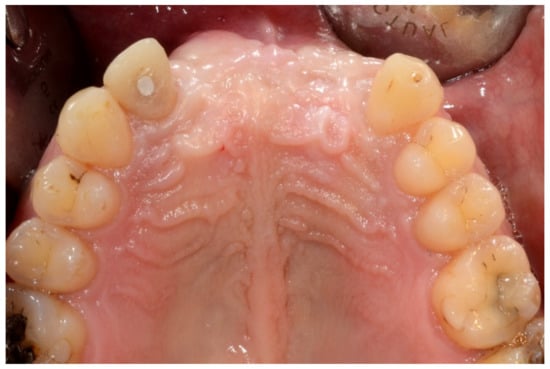

Figure 2.

Occlusal intraoral view showing the edentulous defect.